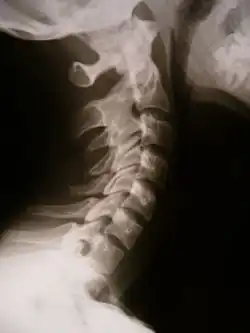

- Синдром Клиппеля — Фейля;

- Блокирование (конкресценция) позвонков, имеющее много возможных вариантов.

В других случаях патологический синостоз возникает на разных этапах дальнейшего роста, например синостоз предплюсны, возникающий в период от 9 до 17 лет. Возможно приобретённое блокирование позвонков при инфекции (туберкулёз, бруцеллёз, брюшной тиф) или неспецифическом воспалении (остеомиелит) и выраженном остеохондрозе в стадии фибротизации диска[6]. Приобретённый синостоз вследствие заболевания сустава называют анкилозом, а созданный в медицинских целях — артродезом.